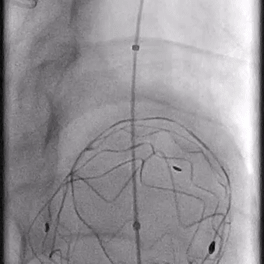

06. 沿右股动脉引入8F长鞘,置入8*50mm Viabahn覆膜支架于开窗处,远端避开左椎动脉,近端超过覆膜支架1cm并完成释放。

07. 最后行全主动脉造影示LSA开窗支架重建良好,近端主体支架定位显影良好,腹主动脉右肾动脉、腹腔干动脉及肠系膜上动脉显影较支架植入前明显改善。

08. 撤出各导丝、导管、鞘管,收紧预埋缝合线,加压包扎各穿刺点。术毕。术后无相关不良并发症。

术后1周复查主动脉CTA显示胸主动脉血管重塑良好,开窗支架形态正常。远端内脏区显影良好。